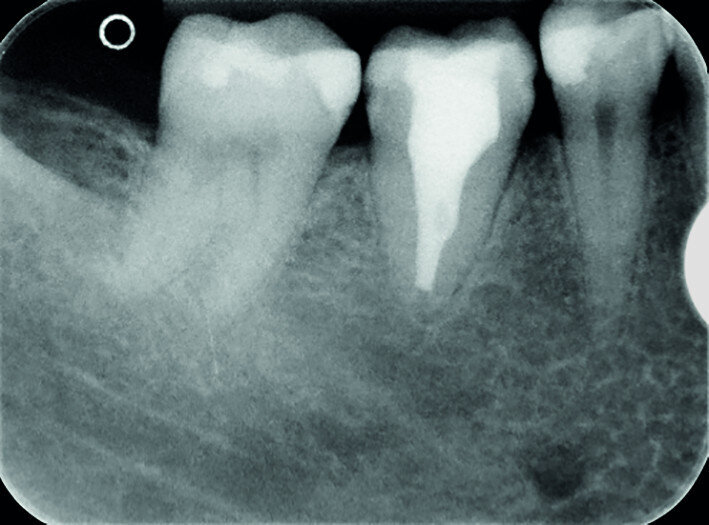

Fig. 16a: Pre-op periapical radiograph.

A 47-year-old male patient in a good medical condition and a non-smoker was referred to our dental practice for endodontic retreatment of the right maxillary second molar. The dental history revealed that the tooth had been endodontically treated three months before because of acute pulpitis. After the treatment, the patient complained of pain on chewing. Antibiotics and a non-steroidal anti-inflammatory drug were prescribed, but the pain remained. After a month, a sinus tract appeared. The tooth was retreated in another practice without success. The clinical inspection revealed the presence of a sinus tract near the apical region of tooth #17. The tooth had been prepared for a full crown, but was without even a temporary crown, and the access cavity had been closed with temporary filling material. Cracks were evident on the buccal and mesial surfaces. Periodontal probing showed a deep pocket (> 12 mm) on the distal aspect of the root trunk (Figs. 1 & 2). The periapical radiograph showed a radiolucency between the roots of the second and third molars. The radiographic appearance of the endodontic treatment was good, without clear evidence of periapical radiolucencies (Fig. 3). A perforation of the pulp chamber floor was suspected. A CBCT scan was performed (Figs. 4–7), and it confirmed the suspicion of perforation, along with the presence of a large periradicular radiolucency and an unfavourable root shape.